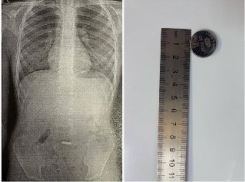

Происшествия Новороссийские врачи спасли мальчика, проглотившего батарейку

Батарейки вызывают химические ожоги – объясняют медики